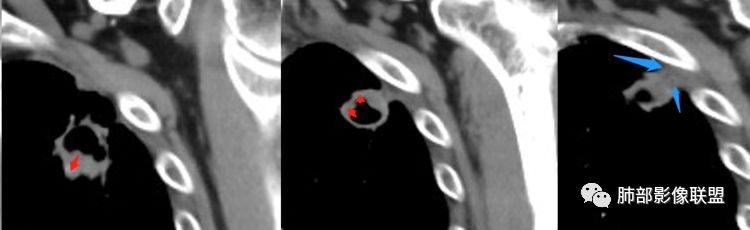

1.左肺上叶应为空腔样病灶。如作为空洞,前下壁并不完整,且与薄壁囊腔壁相延续,整体结合起来看应为厚薄不均匀的较大的空腔样病灶。这样的空腔样病灶应首先怀疑空腔性肺癌。

2.厚壁区可见壁结节及液化坏死。图像未能完整显示小支气管情况,但空腔的存在提示与支气管或多或少还是相通的。

3.病灶轻度环形强化,壁稍显僵硬。灶周显示较清楚,未见磨玻璃晕。

4.可疑胸膜侵犯(栽赃)。

3.内壁凹凸不平。换个视角说,有壁结节,外缘呈分叶状。

4.支气管常截止病灶处,且不会行走厚壁间。

5.轻度或中度环形强化,坏死区不强化。由于破坏性强,加之癌肿生长过快,肿瘤组织压迫供血血管,导致血管阻断、狭窄、血液供应内壁不足,缺血坏死,所以腔壁强化偏弱。

6.胸膜受侵,胸膜外脂肪密度增高;外缘膨隆为主。